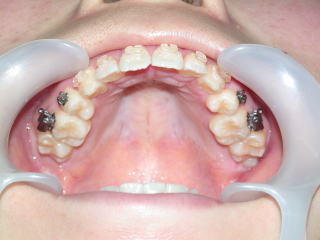

2022年7月25日初診、20代女性の叢生症例 (新潟県長岡市要町 要町歯科 歯科矯正 歯列矯正)

前歯のデコボコが気になる、とのことです。

2023年9月11日